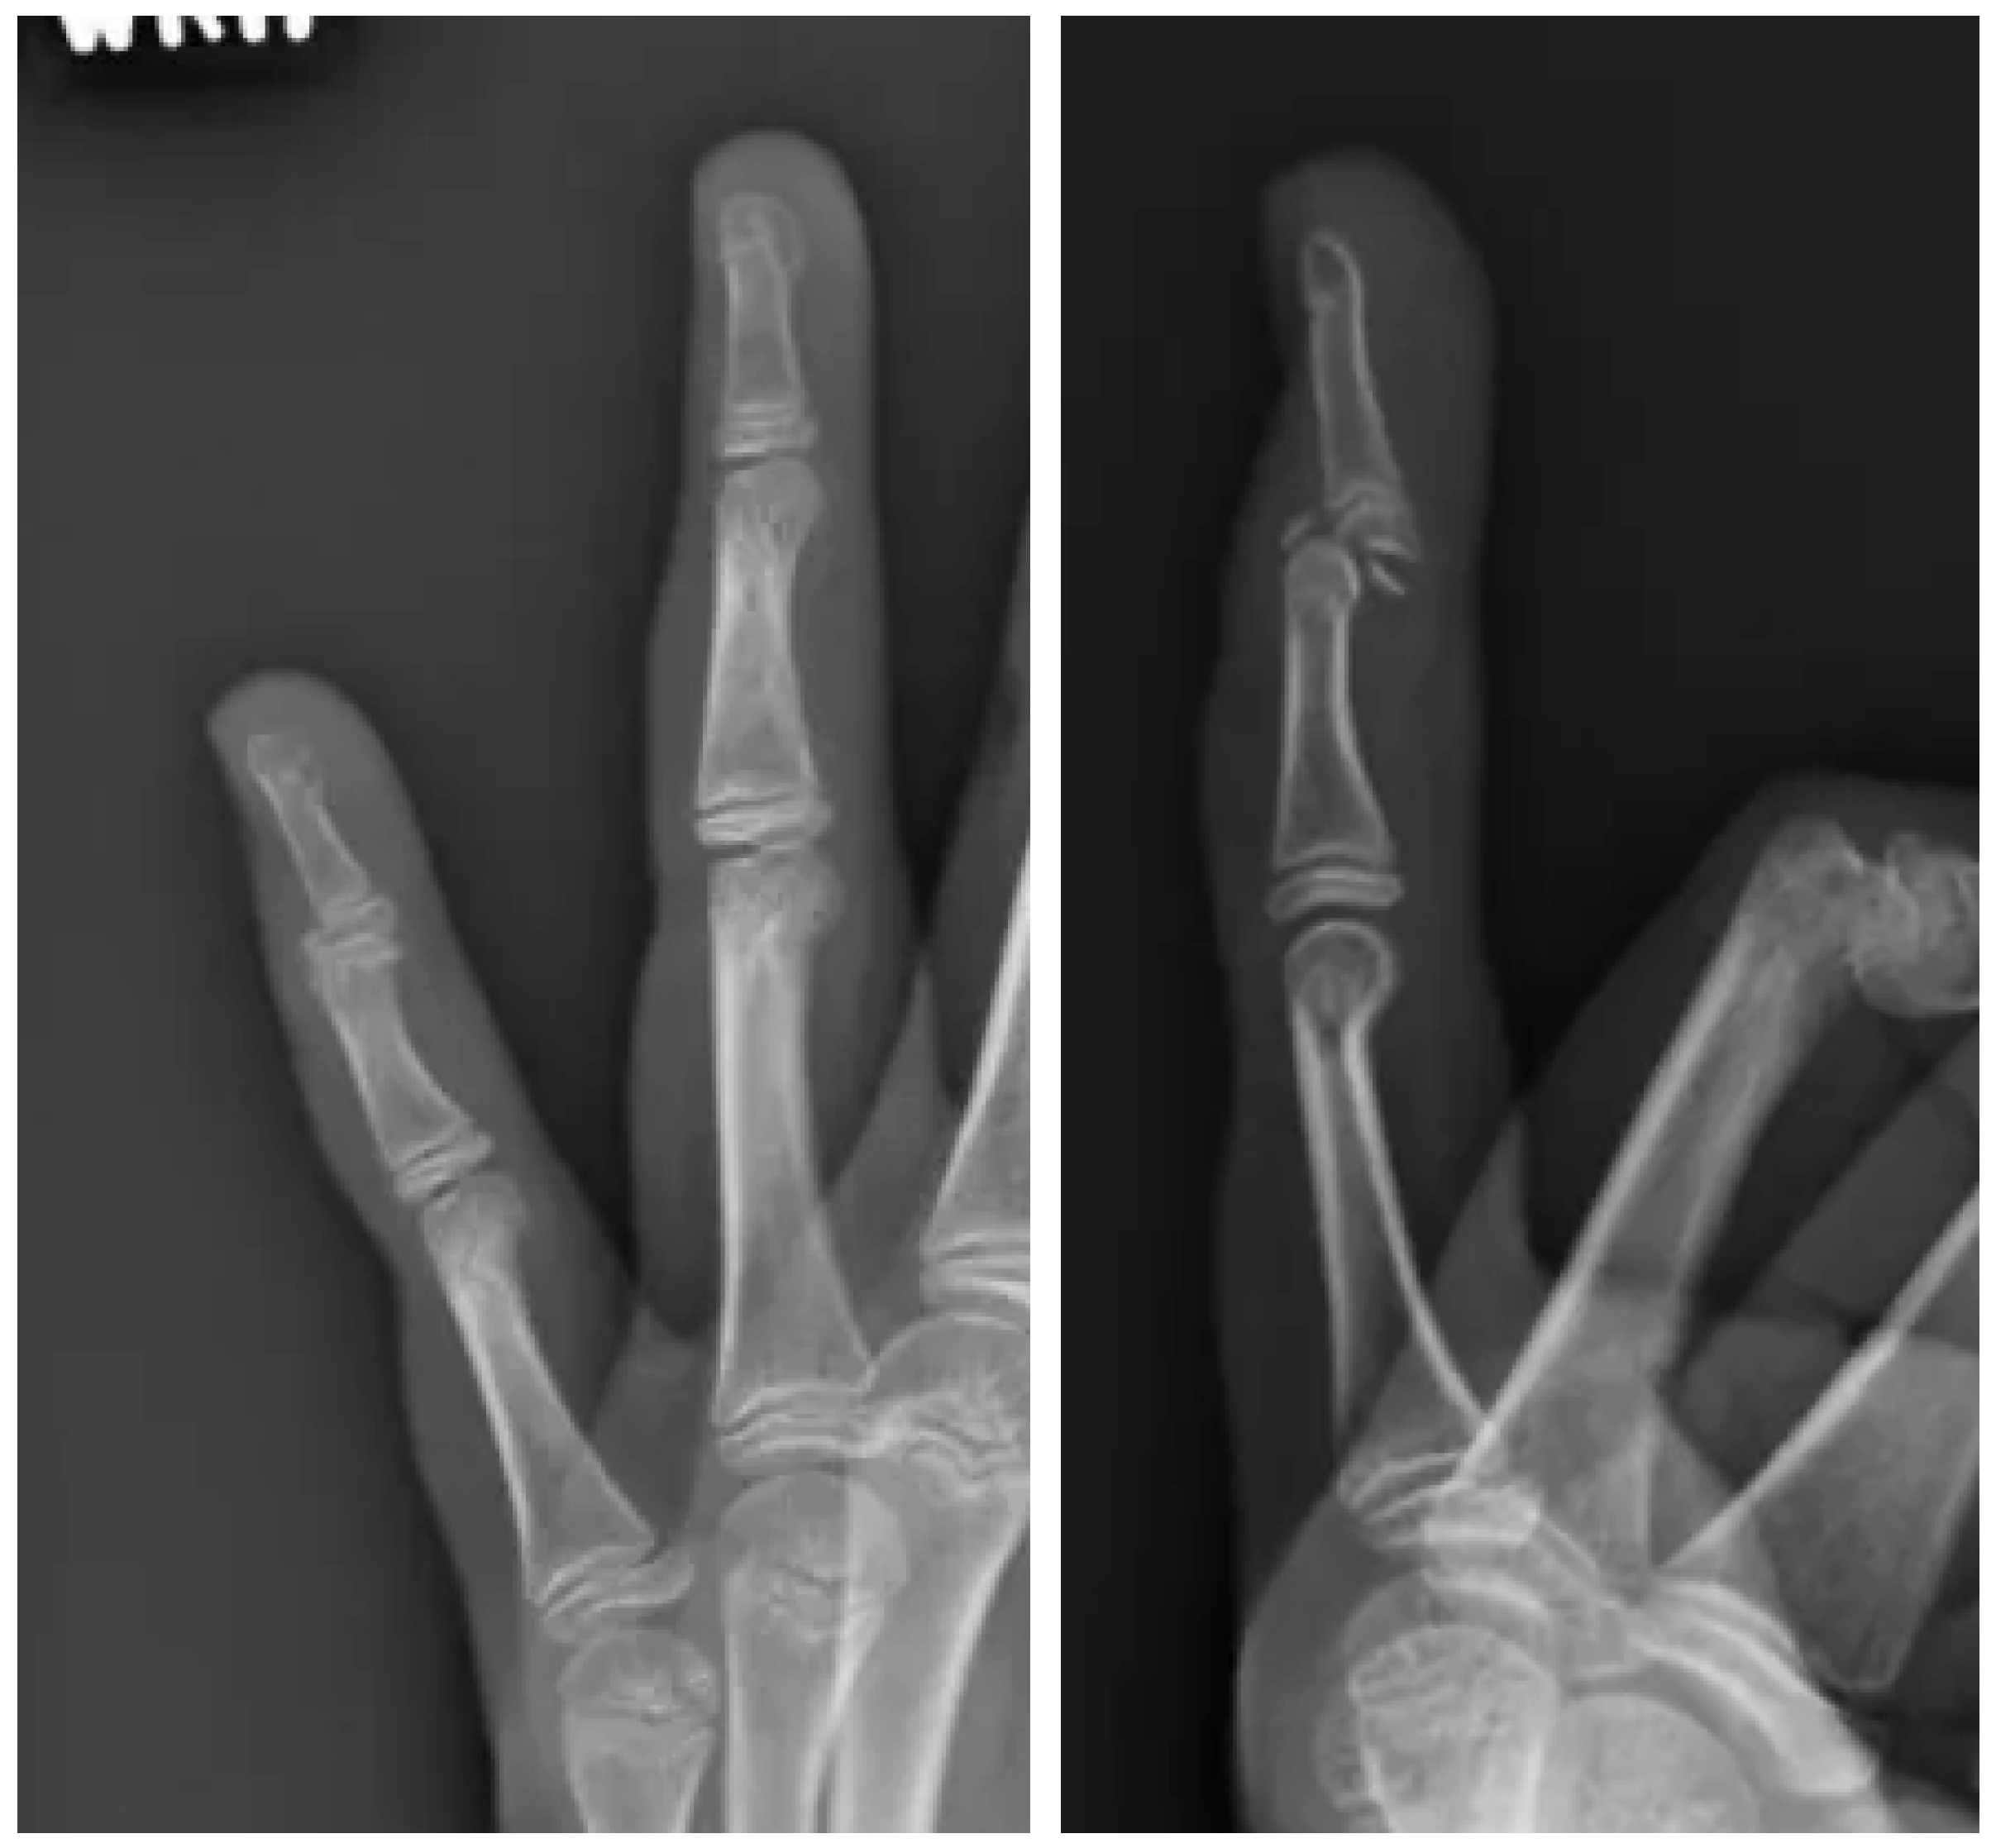

2.1. Surgery

2.2. Follow-Up